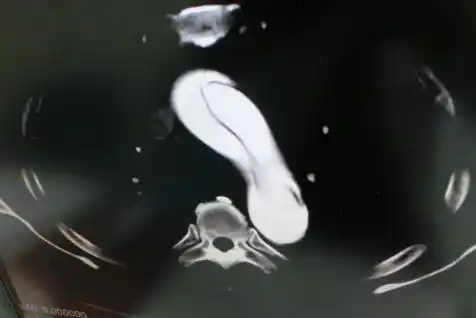

腰痛だけの大動脈解離、

「長距離トラック運転してきた腰痛だけの大動脈解離あり」